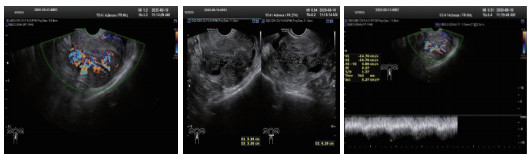

所有患者治疗前行TVDU诊断(图 1),25名诊断UAVF,最终经DSA确诊34名,超声诊断UAVF敏感率为74%,特异率为100%。

| 图 1 经阴道的多普勒超声下UAVF特征性表现 |

TVDU为疾病初筛的手段,敏感度可达74%,特异度100%,可以早期诊断UAVF [11-12]。超声下UAVF特征性表现为无回声区内有丰富红蓝镶嵌血流信号充填,呈“马赛克”或“湖泊样”改变,典型者见静脉血流动脉化表现[12-13]。见图 1。